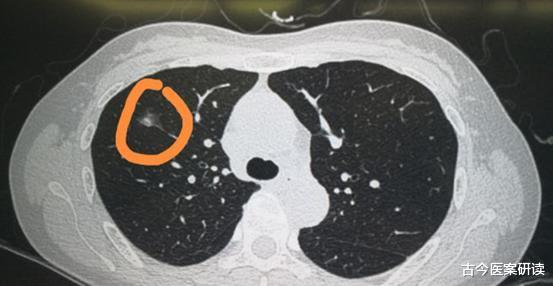

那么结节恶化有哪些表现呢?身体若是没有3种异常 , 肺脏还算健康 。一是根据尺寸 , 结节若是超过8mm , 恶化的可能性较高

二是结节位置 , 多数恶性结节位于肺的右上叶

三是看结节形态 , 结节边缘不明 , 密度形态不均匀 , 不规则恶化可能性高

以大小和性质为主要判断依据 , 形态学作为次要的判断依据 , 是否存在恶变 。